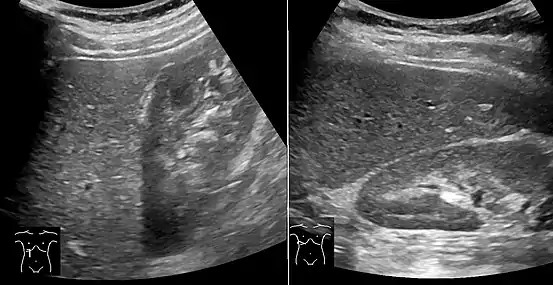

On X-ray computed tomography (CT), the increased fat component will decrease the density of the liver tissue, making the image less bright. Typically the density of the spleen and liver are roughly equivalent. In steatosis, there is a difference between the density and brightness of the two organs, with the liver appearing darker.[12] On ultrasound, fat is more echogenic (capable of reflecting sound waves). The combination of liver steatosis being dark on CT and bright on ultrasound is sometimes known as the flip flop sign.

On abdominal ultrasonography, steatosis is seen as a hyperechoic liver as compared to the normal kidney.

Abdominal ultrasonography with the liver and kidney side by side (left image) may give a false impression of hyperechogenic liver, so it's preferably done with the organ borders facing the ultrasound probe (right image, of the same case).

Abdominal ultrasonography of focal steatosis. It is distinguished from a tumor by not compressing the hepatic vein.